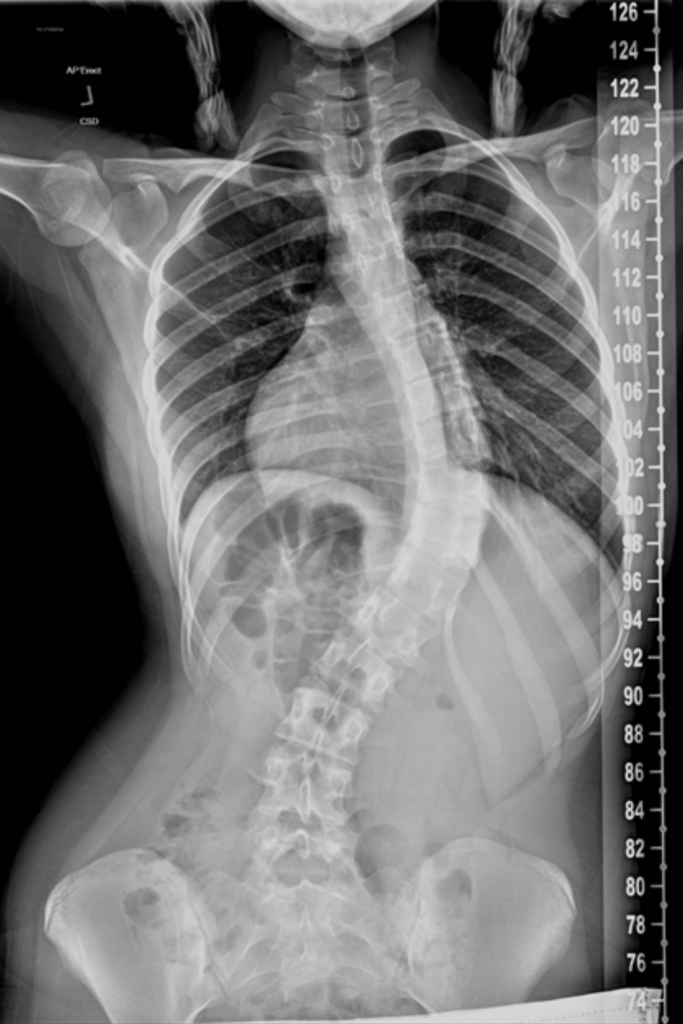

Below is a comparison of before and after images and x-rays of a teenager who underwent surgery due to her scoliosis:

Before |

|